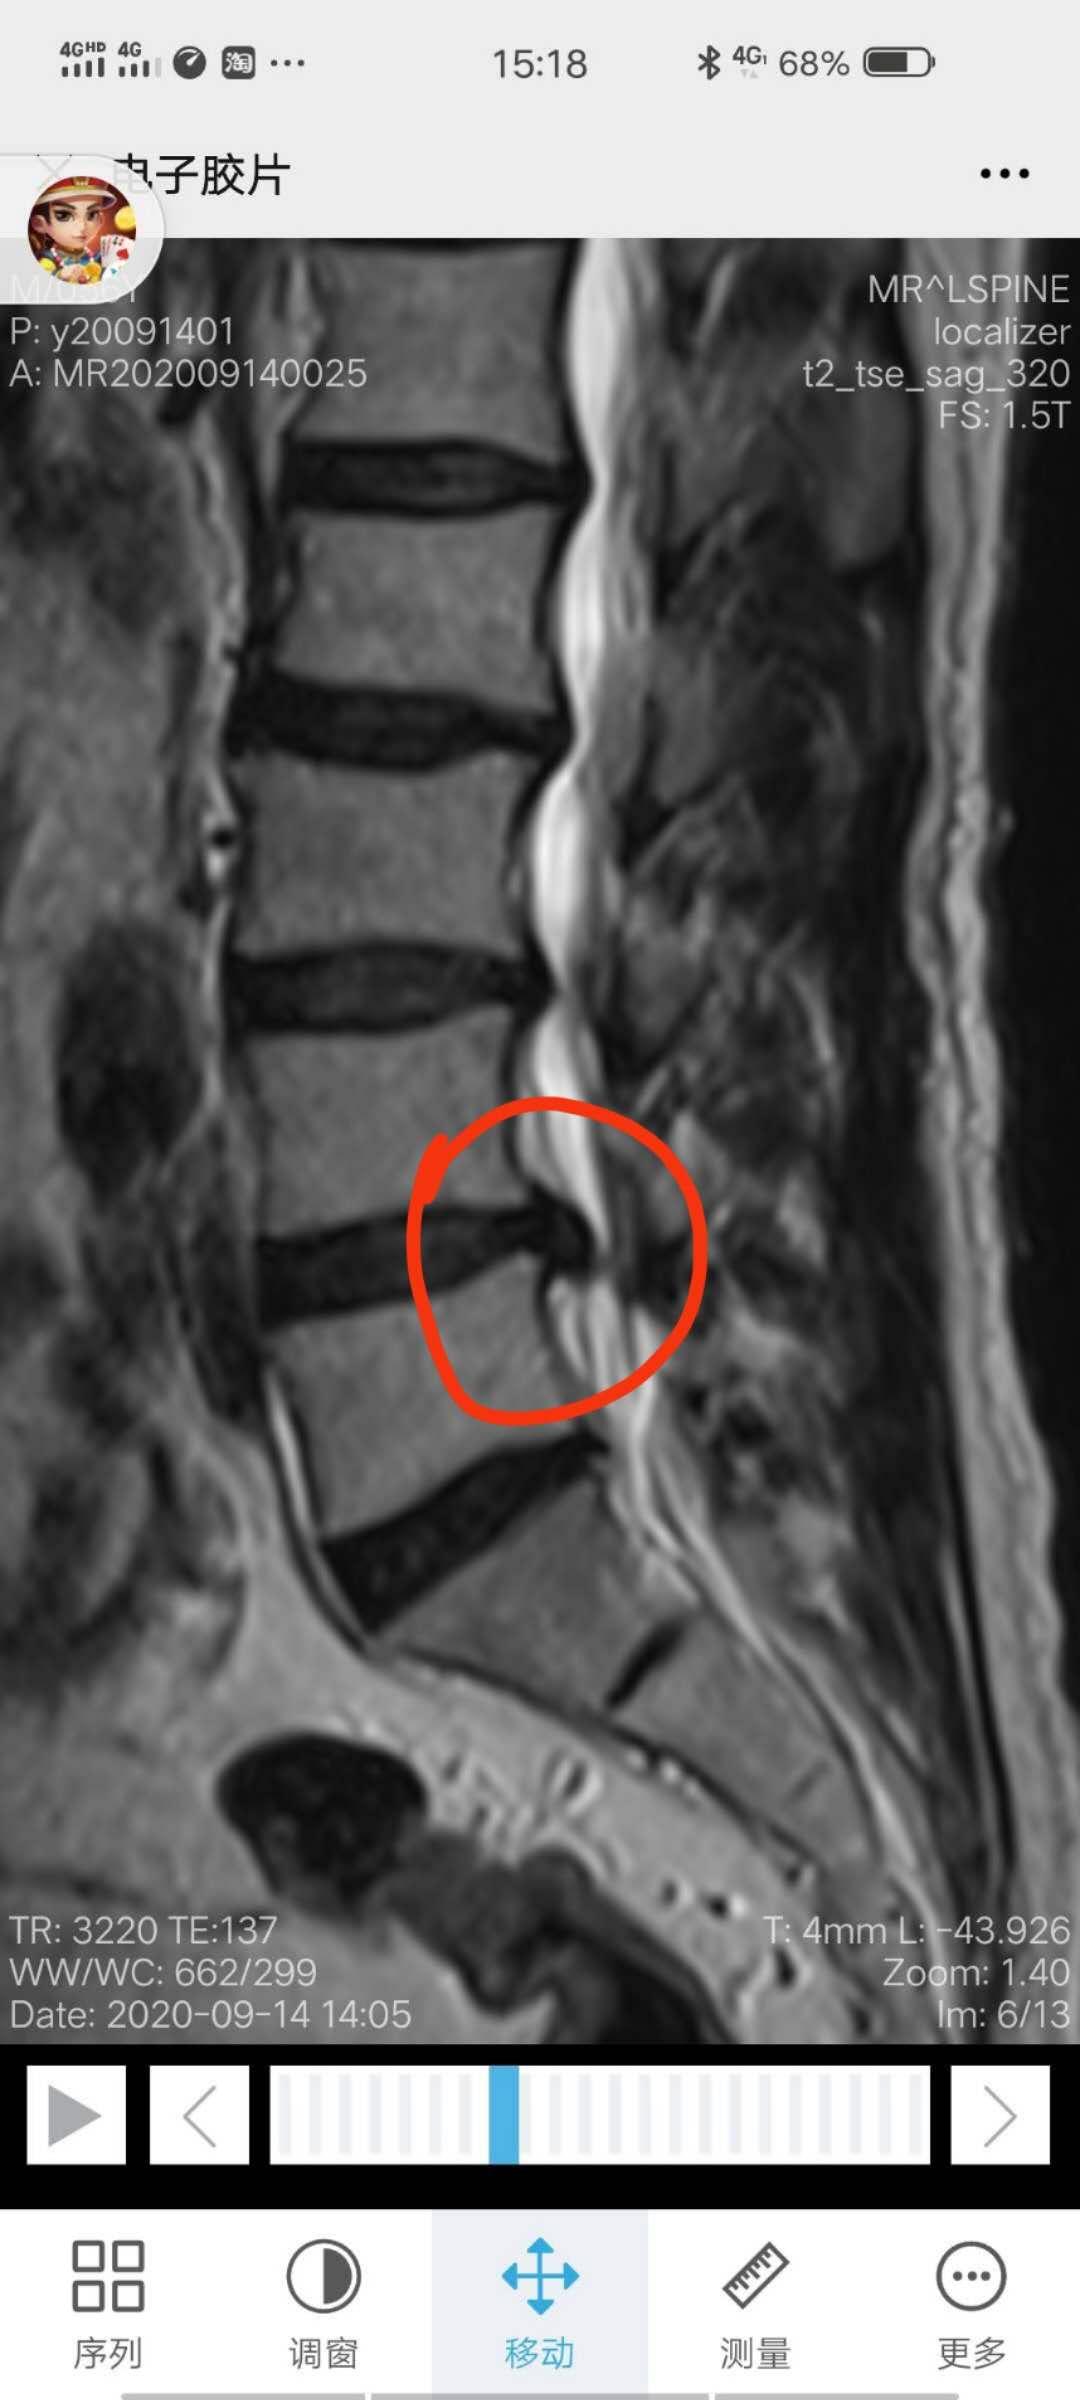

除了“行贿”,痊愈出院的病人又介绍来新的病人,今天收诊的病人中有两位比较特殊的“腰痛”患者,一位是腰痛多年伴右下肢麻痛,并出现间歇性跛行的患者,按双向转诊制度,到上级医院完善相关检查,确诊为“腰椎间盘突出症并椎管狭窄”,明日行腰椎硬膜外神经阻滞暨腰椎小针刀整体松解术,术后行脊柱关节整复,针灸、中药内服、外敷综合保守治疗,按照既往的治疗经验,90%以上此类病人是可以通过综合保守疗法得到缓解,而避免手术的。

另外一位“腰痛”患者是束着腰围来就诊的,其病史更长,20余年曾因为腰部外伤腰椎骨裂后,反复腰痛发作,翻身转侧困难,稍有过度劳累就会出现腰痛加重,病人自述是就像是一种”掉腰“的感觉,没有办法,只能经常带着腰围固定住腰部,仔细查体并行相应辅助检查,查体发现:患者双下肢左短右长,腰椎曲度变直,脊椎腰段压痛叩击痛明显,腰椎左侧最长肌、髂肋肌、腰方肌肌腹及附着点明显紧张压痛,X片检查提示,患者存在腰椎椎体旋转,综合分析,该患者治疗的重点不同于上位患者,病位在椎周而不在椎管内,今日行小针刀整体松解术暨脊柱小关节紊乱整复术,术后,患者诸证若失,接着我们需要做的就是针灸,中药独活寄生汤内服,中药外敷等巩固性治疗了。